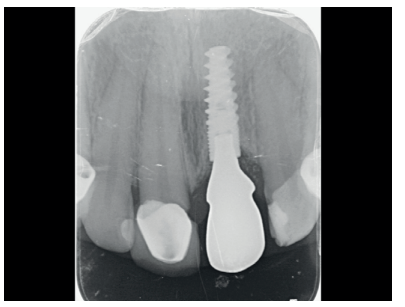

The patient reported pain when chewing in the anterosuperior sector, located in the ICSI area, which disappeared after taking painkillers. An intraoral clinical examination revealed that the decemented crown retained remains of the ICSI stump, as well as a cast post that served as a scaffold for the restoration. The ICSI was a root remnant, with total loss of tooth structure and no ferrule that might ensure a new rehabilitation9 . The patient had a medium smile line and a fine gingival phenotype, which was accompanied by gingival recession in the affected tooth, as well as in the contiguous teeth of the second quadrant. She presented palpation, percussion and a positive bite test and negative vitality in the ICSI, with no periodontal pocket (probe depth < 3 mm) or mobility. An additional radiological examination was carried out, which included a periapical radiograph and cone beam computed tomography (CBCT), see Figure 4. After evaluating these tests, a subgingival complete horizontal coronary fracture without periapical bone involvement was observed.

Proper primary stability was obtained, with anchorage achieved in the residual palatal bone at an insertion torque of 40 N/cm2 . A periapical radiograph was performed to confirm the position (Figure 10).